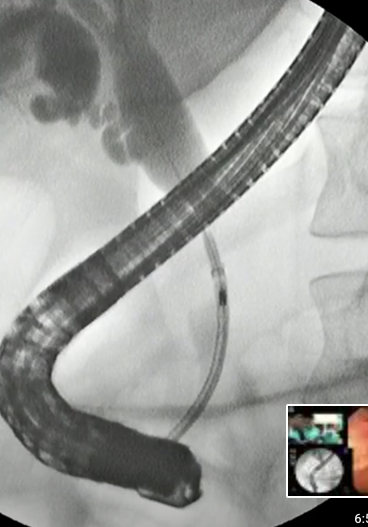

- Videoscopie jusqu’à la papille

- Fluoroscopie pour l’intérieur

Sphincterotome

- le tube qui va dans la papille

- Il peut s’anguler

- Il a un guide (fil) à l’intérieur